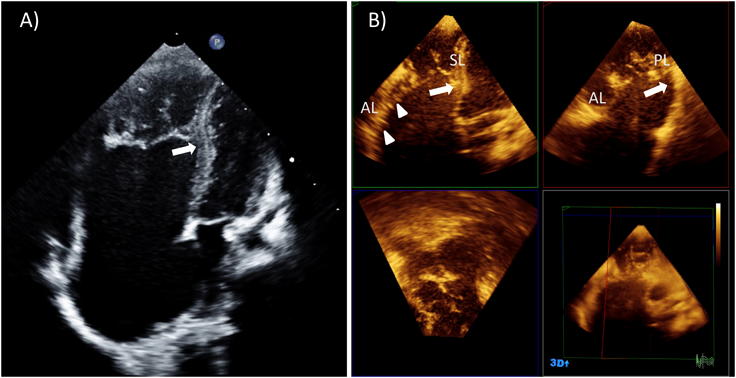

先天性三尖弁異常

1. 正常三尖弁

Fig. 9に新生児の正常三尖弁と経食道3次元エコーでの正常三尖弁を示す.三尖弁は文字通り3弁構造をとるのが通常であるが,正常においても個体間での差異が僧帽弁と比較して大きく,2弁形態や4弁形態をとることもある.三尖弁前尖(anterior leaflet/superior leaflet)は3弁のなかで最も弁葉面積が大きく,前上方に位置し,右室流出路の入り口への暖簾のように存在する.三尖弁中隔尖(septal leaflet/medial leaflet)は前尖に次いで大きい弁葉面積を持つ.中隔尖の腱索は心室中隔から直接起始することから,心室中隔に張り付いた状態で存在し可動性に乏しい.正常の僧帽弁では腱索が心室中隔に挿入することはないことから,中隔尖のこの特異的な形態が三尖弁を特徴づけるものであり,僧帽弁との解剖学的な鑑別点となる.後尖(posterior leaflet/inferior leaflet)は最も弁葉面積が小さく,下壁側に位置する.三尖弁の弁輪には明確な線維性の索状構造が存在しないことが多く,弁の線維性組織はそのまま心内膜下の線維性組織に連続する.特に中隔尖の前方は弁のヒンジ部が房室接合部の高さから心尖方向に偏位したうえで膜様部中隔にそのまま連続することから,弁輪に相当する組織が存在しない.前尖と中隔尖の交連(antero–septal commissure: AS-com)は膜様部中隔の最も頭側に位置し,この交連を支える腱索は通常medial papillary muscle complex(Lancisi’s muscle)(MPM)から起始する.MPMは通常trabecula septomarginalis(TSM)の前腕と後腕の分岐部に位置するが,乳頭筋が複数のこともあれば,乳頭筋構造が全く存在せず,腱索がTSMもしくは室上稜から直接起始する場合もある.前尖と後尖の交連(antero–posterior commissure: AP-com)は右室の鋭縁部に位置し,この交連下に前乳頭筋(anterior papillary muscle: APM)が存在する.この乳頭筋は右室内で最大の乳頭筋であり,基部に調節帯(moderator band)を持つ.後尖と中隔尖の交連(postero–septal commissure: PS-com)は右室下壁と中隔の移行部に存在し,その下部に後乳頭筋(posterior papillary muscle: PPM)が存在する.この乳頭筋は下壁中隔側に存在し,小さい乳頭筋であることが多いがサイズは個体差が大きい16)

Pediatric Cardiology and Cardiac Surgery 33(2): 140-156 (2017)

Fig. 9 Normal tricuspid valve

(A) Normal tricuspid valve of a neonate. (B) Three-dimensional echocardiography of the normal tricuspid valve (atrial view). AL: anterior leaflet; APM: anterior papillary muscle; AS-com: antero-superior commissure; AP-com: antero-posterior commissure; MPM: medial papillary muscle; PAV: pulmonary valve; PL: posterior leaflet; PPM: posterior papillary muscle; PS-com: postero-septal commissure; SL: septa leaflet.